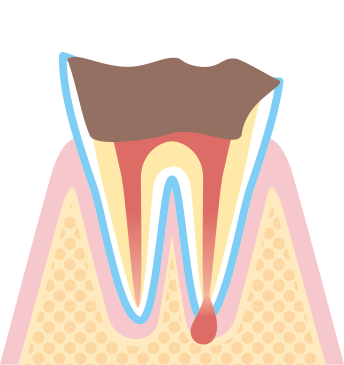

虫歯の過程を分かりやすく説明する表記を専門用語で虫歯を指す「カリエス」の頭文字”C”を用いてC0~C4と段階が付けられています。

段階によって治療内容も変わってきますので参考になさってください。

虫歯部分が歯髄にまで侵食し激しい痛みを伴います。

痛みは一時的なもののため痛みがなくても進行しているケースが多いです。

この場合は、神経の治療が必要になります。

上物はインレー、クラウンなどの治療が必要です。

歯の神経が死んでしまい歯のみならず身体への影響もでてきます。状態によりますが抜歯などの処置が必要なケースも多いです。